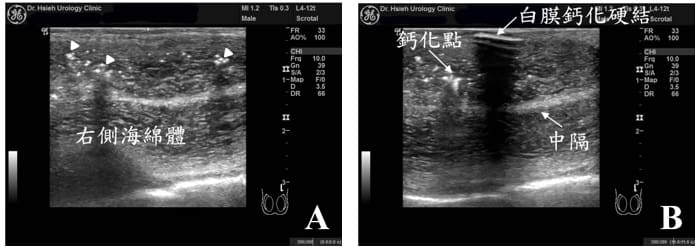

佩諾尼氏症主要源於陰莖白膜遭受壓彎損傷(buckling trauma)或長期性行為造成慢性創傷,導致部分白膜組織纖維化或鈣化,陰莖彩色都卜勒超音波檢查呈現海綿體鈣化(圖2A),白膜上產生斑塊硬結(圖2B),常造成陰莖彎曲、嚴重的沙漏式變形(陰莖兩端粗、中間一段變細)、陰莖長度變短、勃起疼痛、甚至陰莖血管性功能障礙(約佔30%,大多數為陰莖靜脈血管滲漏)、心理挫折焦慮等。如果陰莖彎曲矯正手術前即有勃起硬度的問題,超過30%的患者其術後硬度可能會再降低。因此,手術前陰莖彩色都卜勒超音波檢查評估十分重要。